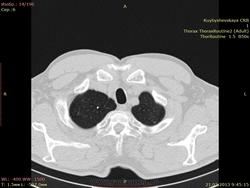

помогите пожалуйста с пациентом. Мужчина 63 года. Примерно месяц назад перенес нижнедолевую пневмонию справа. По рентгенограммам пишут осумкованный плеврит.(есть только описание). Tbc отрицает. что скажете по поводу очагов на верхушках? и справа в н\д описать как спайки?

Ну, кроме явного фиброза в S5 с обеих сторон, в S7 справа и участков эмфиземы легких, действительно, есть какие-то единичные неясные очаги в верхних долях, также внутридольковые плотные очаги в S5 слева и мене плотные и четкие внутридольковые очаги плюс невыраженный фиброз в S10 слева.

Написал бы так, КТ-признаки: бронхопневмонии в S10 левого легкого в стадии неполного разрешения, локального пневмофиброза в S5 обоих легких, S7 правого легкого, эмфиземы легких, очажков неясного генеза в верхних долях обоих легких.  Рекомендуется дообследование на туберкулез, КТ-контроль через 6 мес.

осумкования нет ,справа в нижней доле участок фиброателектаза с проявлениями интерстициального фиброза по периферии,тракцией междолевой плевры(необходимо динамическое наблюдение за участком) ,слева ацино-нодулярные очаги -полечите пробно  и ясно будет.но все таки такие изменения пневмония дать не может -причем бронхопневмония !исключайте активность процесса и включите все гранулематозы в д.д